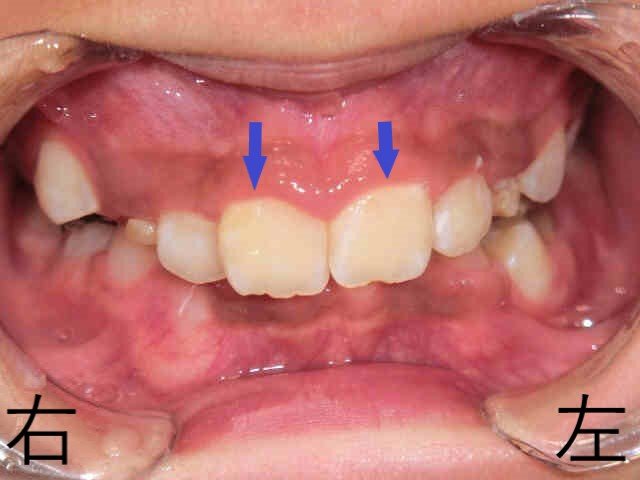

こちらは、マイオブレイスなどの取り外し式矯正装置を用いた小児矯正治療の症例です。治療開始から6か月後の前歯の噛み合わせを撮影した写真をご覧ください。

赤色矢印で示した下顎前歯が、上顎前歯(青色矢印)に隠れていた状態から、下顎の前方成長により前方から見えるようになってきています。

矯正治療前と比較すると、わずか半年で上顎前歯の前突(いわゆる「出っ歯」)が大きく改善され、自然に口を閉じられるようになってきました。